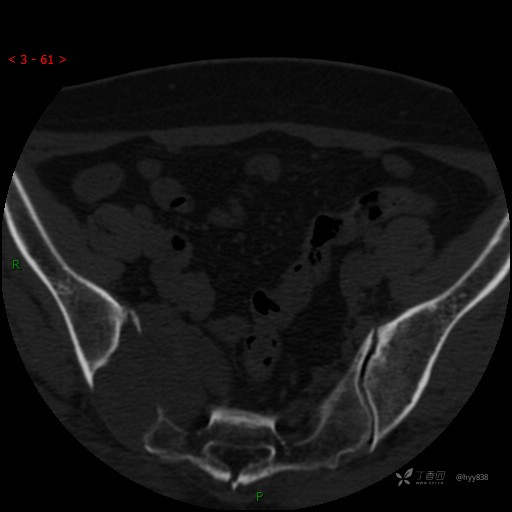

骶髂关节CT平扫